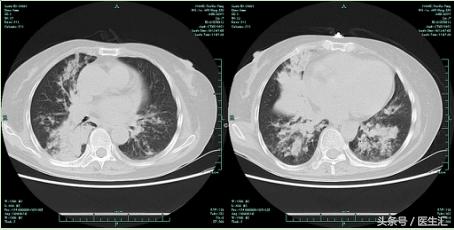

患者20余天前因“胆总管结石”在当地人民医院住院行胆囊切除术,手术过程顺利,术后予舒普深针抗感染治疗。术后一周左右患者出现发热,最高体温39.4℃,发热前有畏寒及进食呛咳,伴有阵发性咳嗽,咳黄白痰,痰液时有拉丝状,伴大汗淋漓,无夜间盗汗,无胸闷气急,无胸痛咯血,无恶心呕吐,无腹痛腹泻等不适。查肺CT示:两肺散在炎性改变,部分实变,右肺为甚。遂予改用阿奇霉素针及哌拉西林他唑巴坦针抗感染治疗,患者上述症状无明显缓解,复查肺部CT提示病灶无明显改善。痰培养提示阴沟肠杆菌及少量霉菌孢子。遂改用替考拉宁针和美罗培南针抗感染治疗,患者出现全身皮疹,遂予以停药,改用左氧氟沙星及氟康唑抗感染治疗,咳嗽咳痰仍明显。经我科会诊后,遂转至我院,为求进一步明确诊断及治疗,拟“肺部感染,胆囊切除术后,脑梗后遗症”收住入院。

肺部CT检查

10天后复查肺CT:肺部病灶略有吸收

1月 后复查肺CT 肺部病灶明显吸收